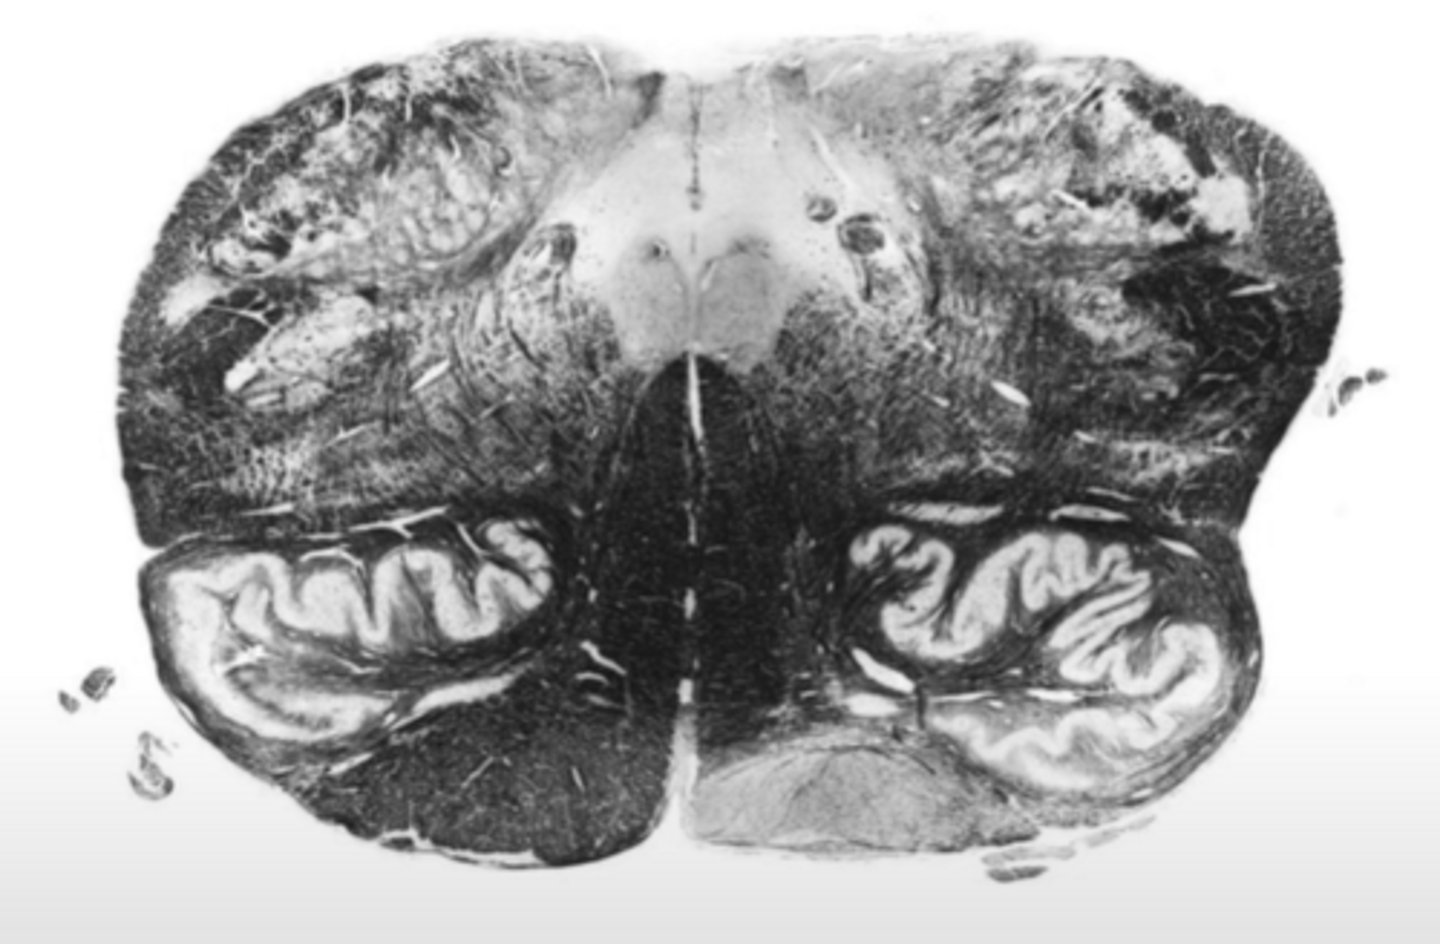

hypoglossal nucleus

ID the nucleus

vestibular nucleus

inferior cerebellar peduncles

ID the structure

reticular formation

vagus nerve

ID the nerve

principle olivary nucleus

corticospinal fibers

hypoglossal nerve

medial lemniscus

anterior median sulcus

fourth ventricle

ID the space